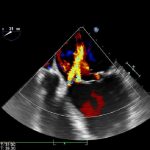

Si chiama EcovidUS è un ecografo portatile che permette di diagnosticare con grande accuratezza la polmonite da Covid e monitorarla nel tempo. Questo ecografo portatile ed è stato messo a punto nell’Istituto di Fisiologia clinica del Consiglio Nazionale delle Ricerche (Ifc-Cnr) di Lecce. L’esame diagnostico si basa sul posizionamento di 14 sonde sul torace e sui dati che, all’istante, vengono confrontati con migliaia di altre immagini ecografiche e danno il risultato in pochi minuti.

Non c’è bisogno di un medico ma solo una breve formazione su dove posizionare la sonda. Lo strumento è portatile e spesso può essere più utile di un tampone, nei casi in cui il paziente sia ancora asintomatico ma presenti lesioni polmonari e l’affidabilità raggiunge il 90%.

«Il sistema EcovidUS, grazie all’interfaccia operatore estremamente evoluta e basata sui più innovativi algoritmi e criteri di analisi automatizzata della bioingegneria ̶ spiega Marco Di Paola, medico ricercatore dell’istituto ̶ consente di eseguire un esame estremamente affidabile, fornendo, senza l’intervento dell’operatore stesso, la diagnosi obiettiva sullo stato polmonare del paziente, permettendo di associare un indice numerico allo stato di gravità della polmonite (Pneumonia Index), e riuscendo anche a distinguere se la stessa sia dovuta al Covid-19 o meno (Covid Index)».

L’ecografo è utilizzabile in ogni contesto, persino a casa del paziente o presso gli studi dei medici di famiglia. «In sostanza ̶ rileva Di Paola ̶ EcovidUS non richiede al medico alcuno sforzo interpretativo, fornendo una diagnosi polmonare basata su un indicatore numerico obiettivo». Gli algoritmi proprietari, spiega il ricercatore, sono stati validati clinicamente su oltre 500 pazienti (sani e malati), mostrando un’elevata sensibilità e specificità (superiori al 92%) nel discriminare i pazienti sani da quelli malati. Alla sperimentazione e validazione clinica ha partecipato, fra gli altri, anche un folto team di medici del Dipartimento emergenza-accettazione di Lecce dove il dispositivo è stato già adottato. ABov